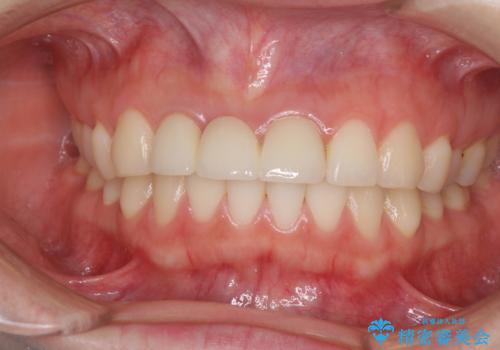

また、歯とクラウンの境目が合っていない部分が多く、歯肉からの出血が認められました。

金属色の透けた感じも歯肉からの出血もなくなり、自然な仕上がりの前歯となったので、患者様には大変満足していただきました。